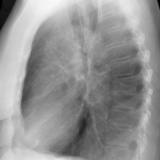

RLL Collapse  1 Lateral

Date: 02/28/2004

Views: 3183